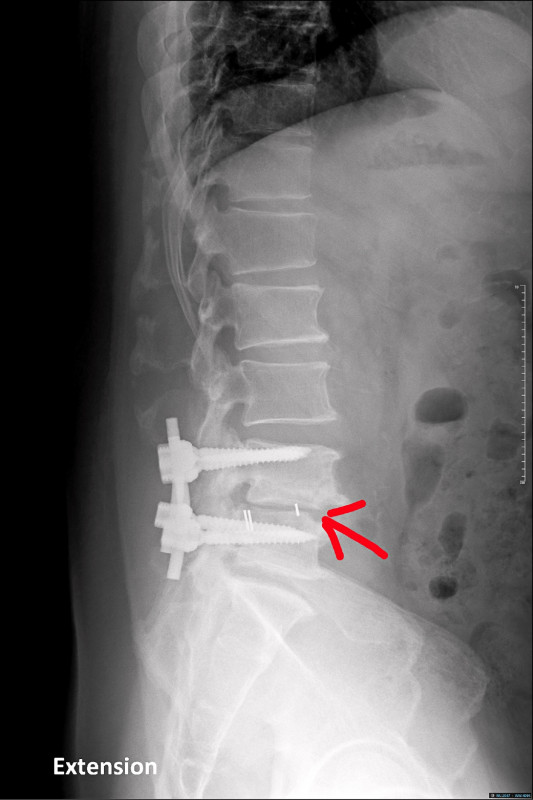

因為前述症狀,前來林口長庚醫院脊椎科門診。先幫他安排脊椎X光檢查,可以看到之前手術的釘子有鬆脫的情形(圖1),同時人工椎間盤墊片有向後外側滑脫的情形(圖2)。後續幫吳先生安排腰椎核磁共振(圖3),發現人工椎間盤墊片有向後壓到神經。吳先生的症狀和影像上的發現是相符的,因此向他解釋後續治療的方向。